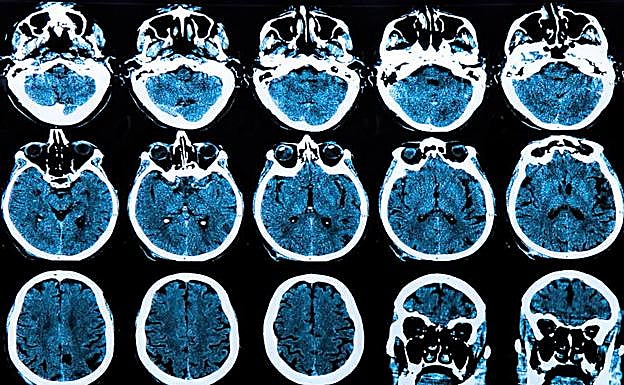

Escaner cerebral de un paciente. Archivo

Investigadores descubren el secreto de la «inmortalidad» del cáncer cerebral

A diferencia de las células sanas, que están estrictamente limitadas en la cantidad de veces que pueden dividirse, las células cancerosas pueden seguir dividiéndose y multiplicándose para siempre